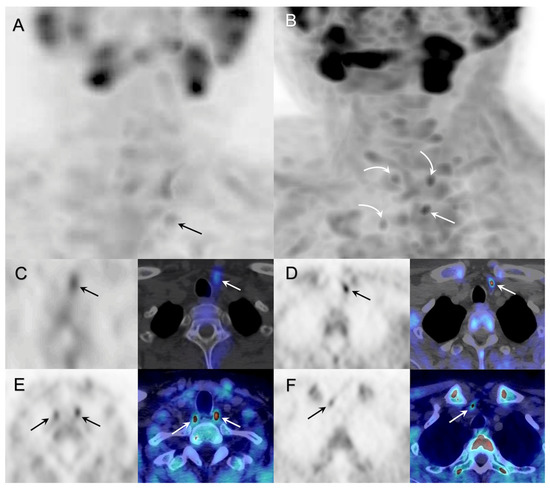

3.2. Parathyroid Imaging